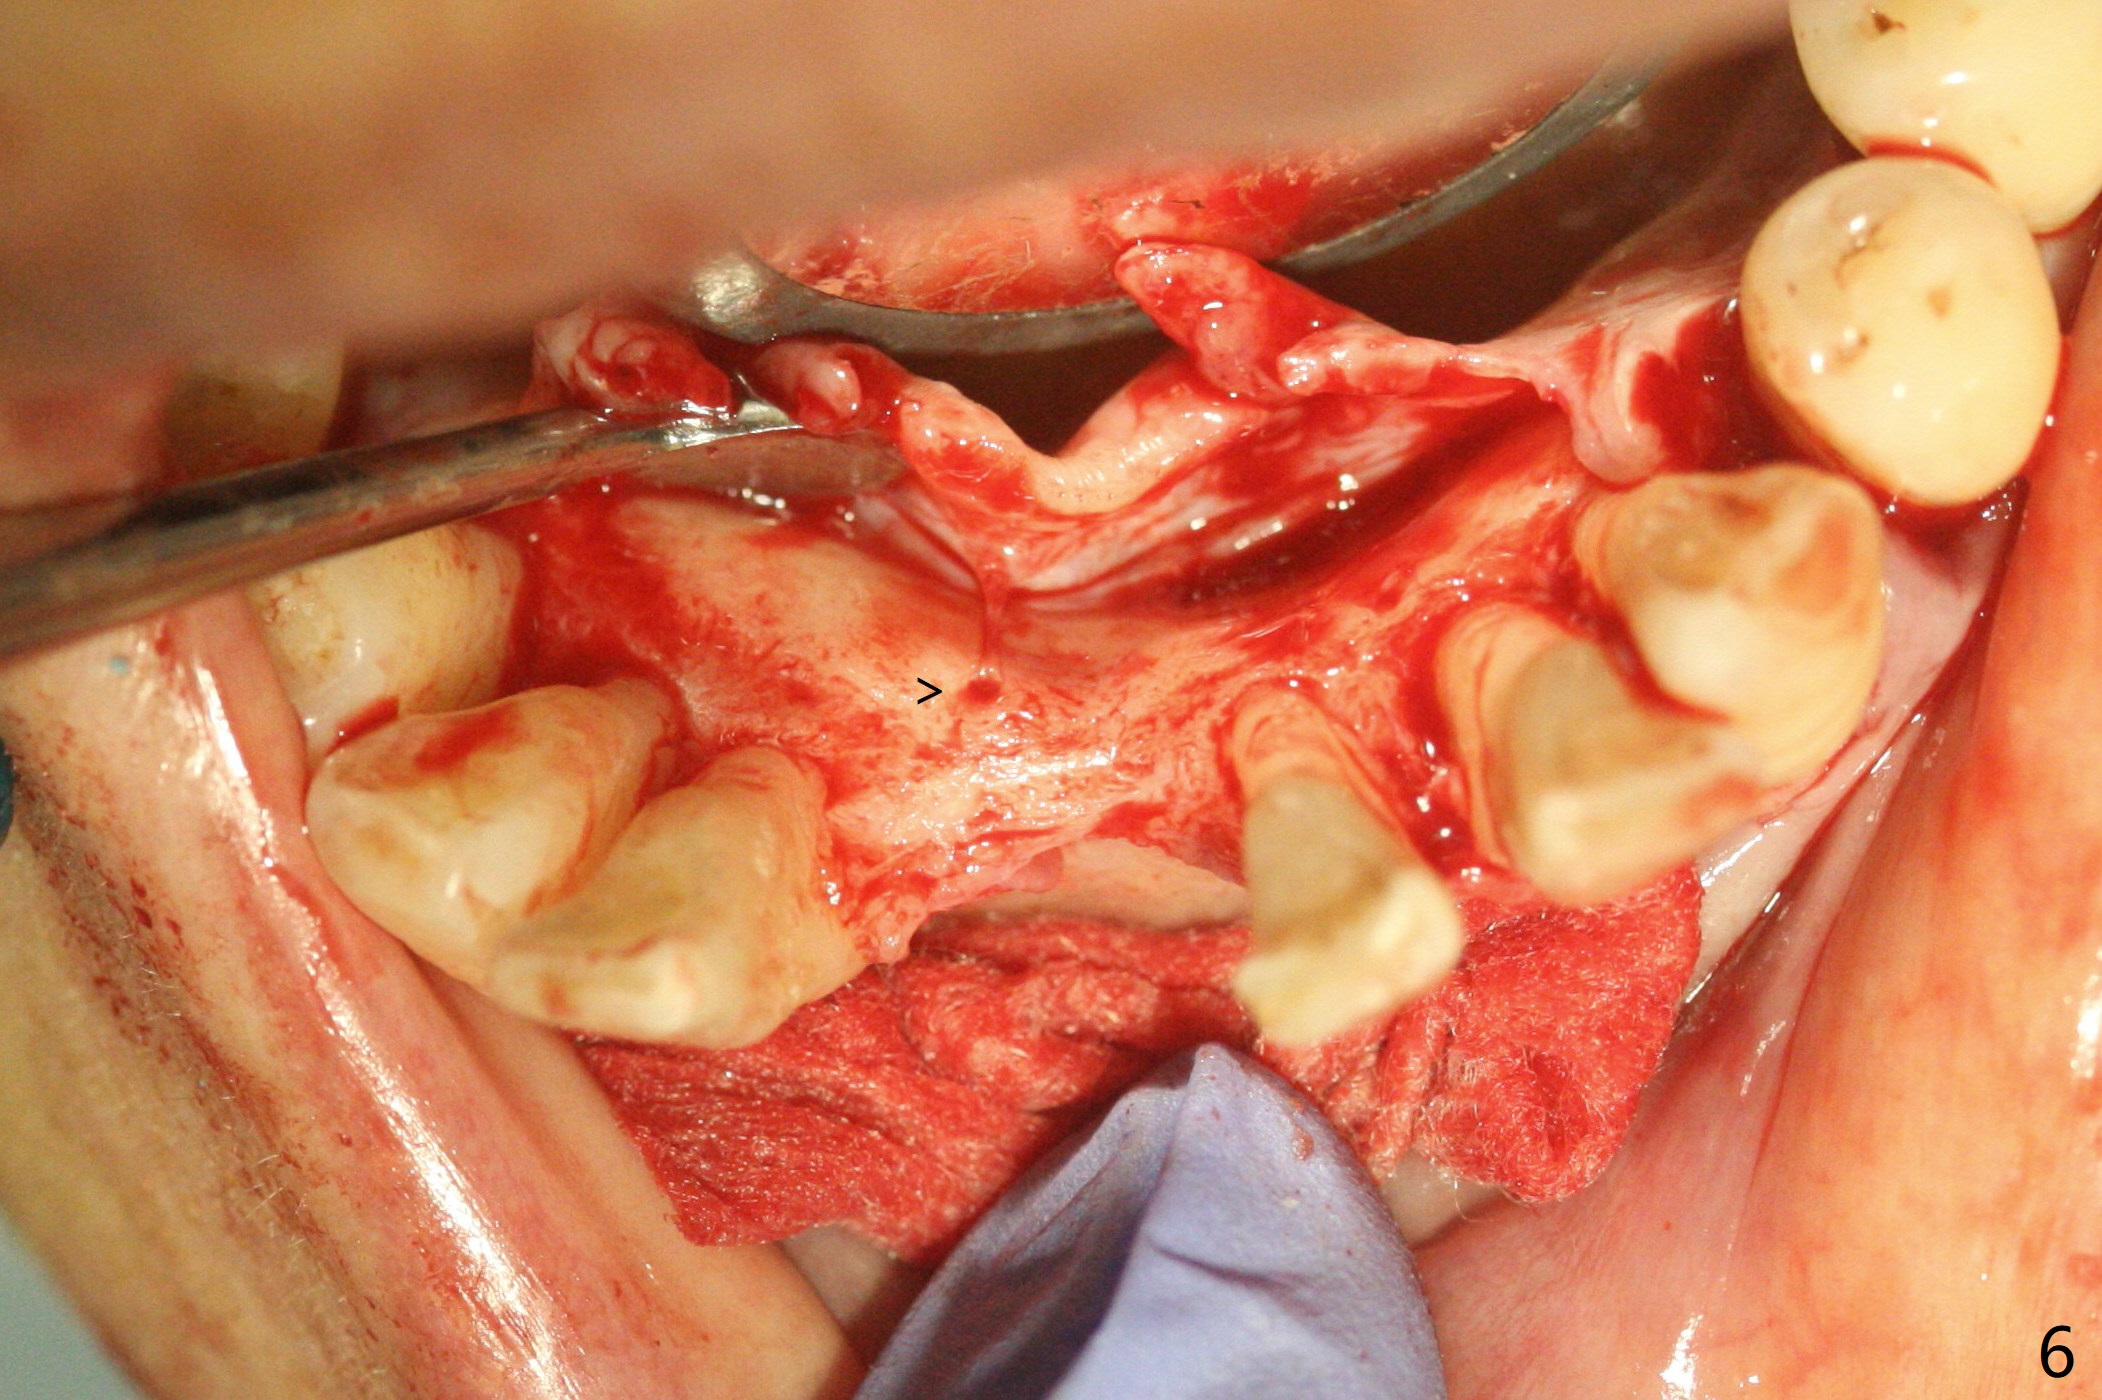

56岁女十分恐惧治疗,缺失右下1,其余切牙由于骨质吸收颊侧移位(图一:1,2),但是她不愿意拔除,同意右下1种植,牙周骨手术,植骨;植体整合后作为支抗,矫正移位下门牙。为了防止忘记舌侧瓣分离,先做舌侧切口(图二),然后颊侧瓣松弛分离(图三),包括使用前牙隧道刀(图四)切断颊侧骨膜,松弛到颊侧瓣能向舌侧牵拉3-4毫米(图五),舌侧瓣骨膜下广泛,深部分离(好像不能切断骨膜,图六),放置导板,磨平狭窄的牙槽嵴(图七:O(osteotomy)),植入2.5x12(4)毫米一段式植体(图八:故意舌侧植入,以便以后矫正),在颊侧骨板打多个出血洞(图八:箭头),然后把在平的器皿上形成的粘性骨板(sticky bone,图九),放置于植体和移位切牙周围(图十),接着使用消毒过的橡皮障punch(图十一(纸头相当于PRF膜;事先给助手示范))在三个PRF膜(图十二)打洞,套在植体和门牙上(图十三: 箭头),防止膜(图十四)和骨块(图十五,十六:*)移位,最后还必须使用最原始方法牙周敷料保护伤口(图十七)。术后9天,舌侧牙周敷料脱落,伤口稍微裂开(图十八)。术后18天撤除敷料,伤口裂开处有新鲜肉芽组织生长(图十九(*:下面是填入的骨粉,将是增宽的牙槽嵴(如果你是乐观主义者)),二十)。病人十分感激我们帮助她度过难关。她的确有sleep apnea,否定tongue thrust。术后三个月植体周围没有明显骨质吸收(图二十一至二十三),左下1,2轻度反合(图二十四),植体周围软组织健康(图二十五),5-5安置矫正器(图二十六,二十七,12 niti)。一周后下切牙向舌侧移动(图二十八),左下1,2反合纠正(图二十九)。再一周变化不大(图三十),植牙圈有些松动,两周后将重做临时牙冠,槽往舌侧移动。结果病人提前回来,植牙槽舌侧移位。一周后右下2不适(图三十一),尝试近中牵引(图三十二)。